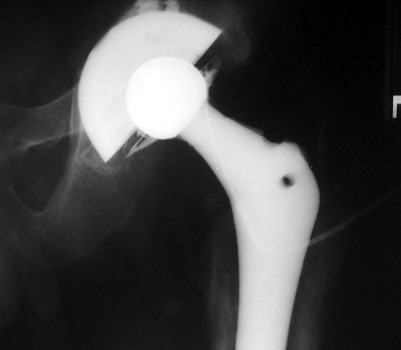

Arthrographic evidence of looseningcontrast enters

abnormally widened interface Gruen zone 1 and 2